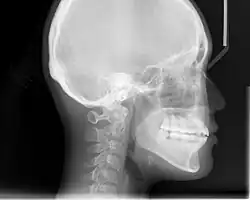

Cephalometric radiographs

Cephalometric analysis depends on cephalometric radiography to study relationships between bony and soft tissue landmarks and can be used to diagnose facial growth abnormalities prior to treatment, in the middle of treatment to evaluate progress, or at the conclusion of treatment to ascertain that the goals of treatment have been met.[5] A Cephalometric radiograph is a radiograph of the head taken in a Cephalometer (Cephalostat) that is a head-holding device introduced in 1931 by Holly Broadbent Sr. in USA.[6] The Cephalometer is used to obtain standardized and comparable craniofacial images on radiographic films.

Lateral cephalometric radiographs

Lateral cephalometric radiograph is a radiograph of the head taken with the x-ray beam perpendicular to the patient's sagittal plane. Natural head position is a standardized orientation of the head that is reproducible for each individual and is used as a means of standardization during analysis of dentofacial morphology both for photos and radiographs. The concept of natural head position was introduced by Coenraad Moorrees and M. R Kean in 1958[9][10] and now is a common method of head orientation for cephalometric radiography.[11][12]